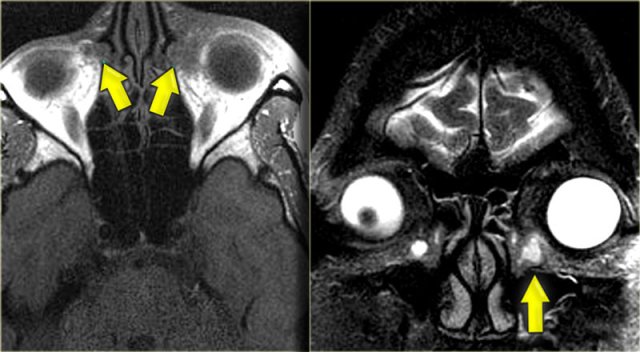

Left is an axial T1WI, right is a coronal T2WI.

There is an abnormality on the left side, but to a lesser degree also on the right.

The yellow arrows point to the naso-lacrimal ducts.

The naso-lacrimal sac connects with the duct, which then drains into the inferior meatus.

On the left there is peri-orbital pre-septal soft tissue swelling.

On the coronal image there is bilateral high signal at the junction of the nasolacrimal duct and sac, indicative of a fluid collection.

On the left side there is also edema of the surrounding tissue.

Post-contrast T1WI, axial and coronal.

Lateral to the naso-lacrimal ducts on both sides, there are the fluid collections which now show peripheral enhancement.

The additional images (T2WI) show mucosal disease of the right maxillary sinus and a fluid level in the left maxillary sinus, in addition to extensive ethmoidal and sphenoidal sinus disease.

This patient had acute sinusitis which was complicated by orbital cellulitis and dacrocystitis with abscesses.

Developmental or inflammatory narrowing of the naso-lacrimal duct is a risk factor for developing dacrocystitis.